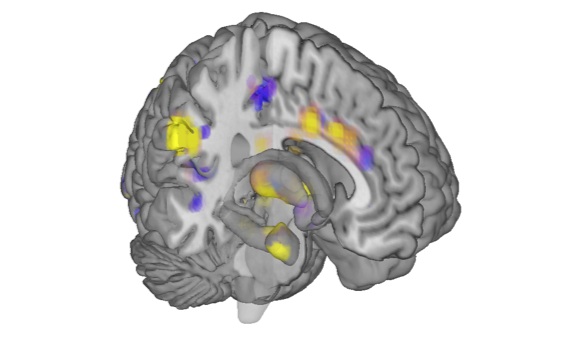

By feeding all of these scans into a computer program, Wager and his team discovered a pattern in the brain scans, common to the participants, that showed up only for painful heat. Using this pain signature, they were then able to evaluate people’s pain in response to particular levels of heat with 90 to 100 percent accuracy, Wager says.